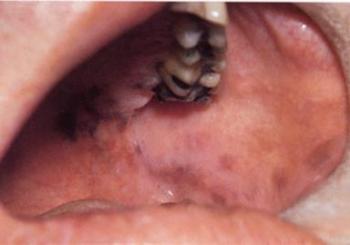

8.7.1. A szájnyálkahártya melaninos pigmentációja